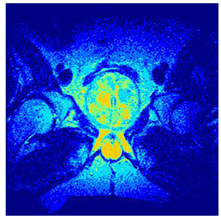

| Image | nt = 3 | nt = 4 | nt = 5 | nt = 8 |

|---|---|---|---|---|

| 1 | ![]() | ![]() | ![]() | ![]() |

| 2 | ![]() | ![]() | ![]() | ![]() |

| 3 | ![]() | ![]() | ![]() | ![]() |

| 4 | ![]() | ![]() | ![]() | ![]() |

| 5 | ![]() | ![]() | ![]() | ![]() |

| 6 | ![]() | ![]() | ![]() | ![]() |

| 7 | ![]() | ![]() | ![]() | ![]() |

| 8 | ![]() | ![]() | ![]() | ![]() |

| 9 | ![]() | ![]() | ![]() | ![]() |

| 10 | ![]() | ![]() | ![]() | ![]() |

| 11 | ![]() | ![]() | ![]() | ![]() |